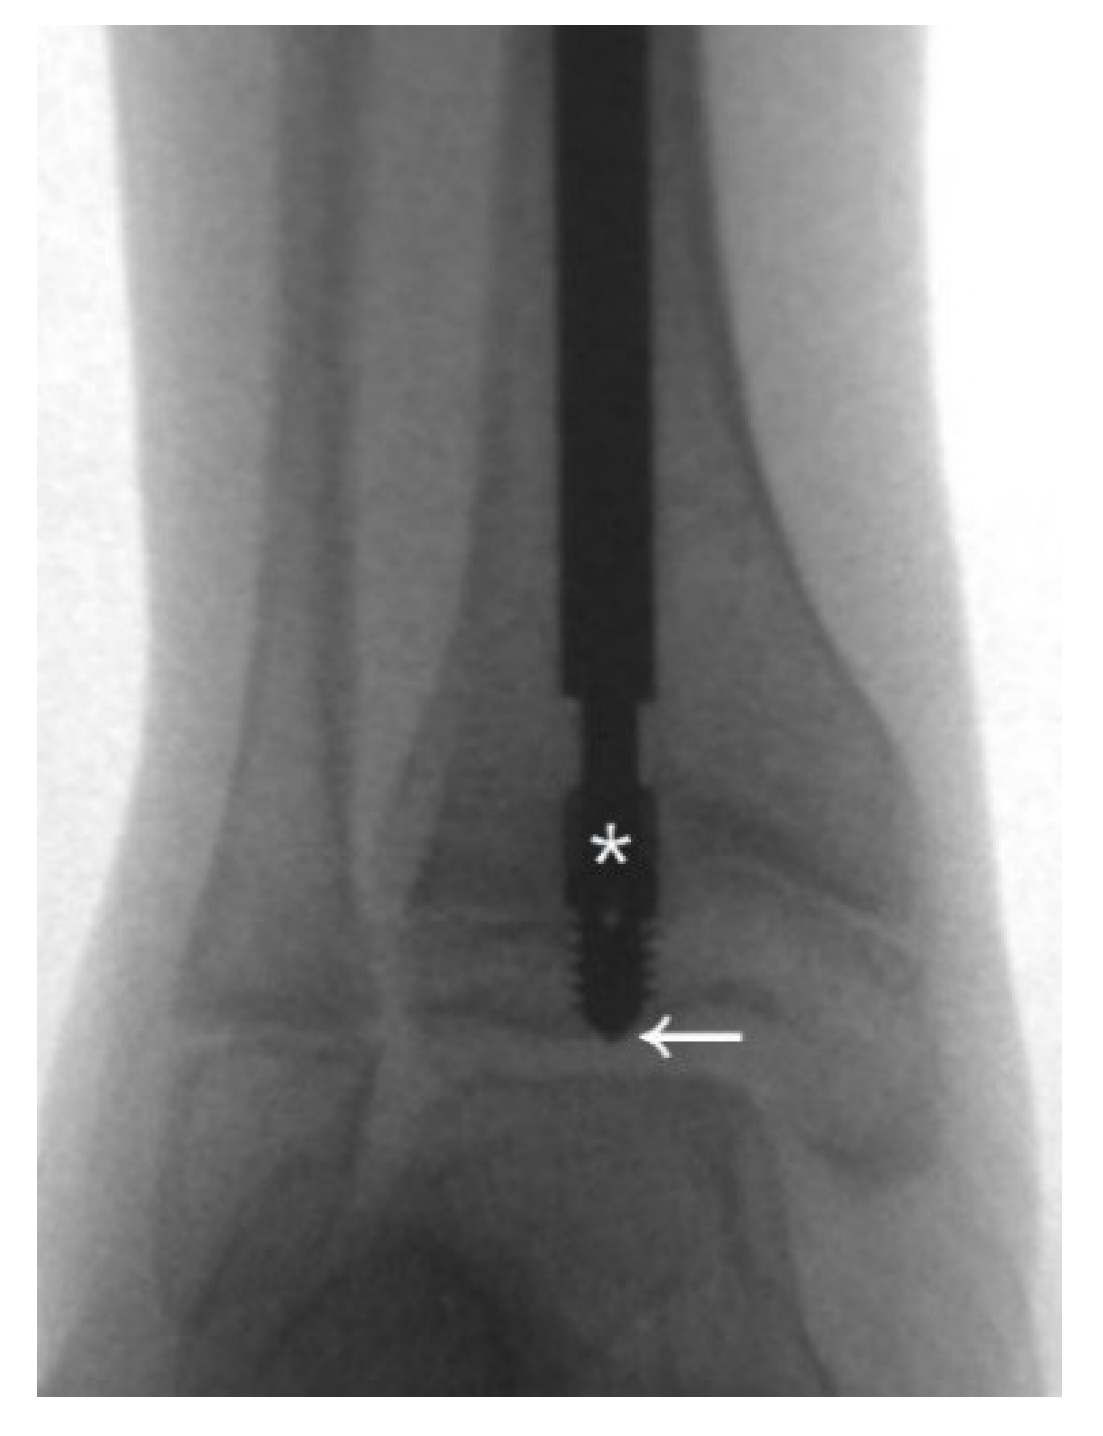

Another of our cases involved a boy who received double osteotomies and fixation with an FD nail in his right femur at the age of 1.5 years (Figure 3). The proximal osteotomy segment was too small to align and the greater trochanter had not ossified, so it was difficult to find the most suitable entry point under the c-arm (Figure 3a). During follow-up, we found that the female thread had become much more distal and anterior (Figure 3b). In the following revision, due to concerns over damaging the apophysis of the femur and iatrogenic greater trochanter epiphysiodesis, with resulting sequela of valgus deformity, insufficient depth of the female component may have occurred, resulting in its proximal protrusion (Figure 3c,d). The importance of the entry point and adequate purchase of the proximal femur cannot be over-emphasized (Figure 3e).

Figure 3. Anteroposterior (AP) view radiograph of the femur of a 1.5-year-old male post FD nail implantation. (a) The boy received double osteotomies and fixation with an FD nail in the right femur. The proximal fragment was extremely small and difficult to control, and the greater trochanter had not yet been ossified, so it was a huge challenge to find the most suitable entry point under the c-arm. We can see the entry point was anterior to the true position of the greater trochanter. (b) During regular follow-up, we found that the female thread had become much more distal and anterior with nail bending. (c) In the revision surgery, due to concerns over damaging the apophysis of the femur in order to avoid physis fusion and valgus deformity, we may have used insufficient depth of the female component. (d) During regular follow-up, we found proximal protrusion of the female component. (e) Good position and adequate purchase of the FD nail post revision surgery.